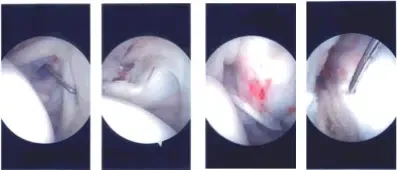

Intraoperative Arthroscopy Images

The arthroscope was removed and re-inserted into the subacromial space. A shaver was introduced from the anterosuperior portal. A Bursectomy was performed. Examination of the rotator cuff showed a partial rotator cuff tear on the bursal side. There was no fraying of the acromion.

The AC joint did not show any arthritis. Decision was taken not to do distal clavicle excision. The plane of the rotator cuff tear was implanted. Lateral entry anterior portal was made. We completed the bursectomy.

The implant was introduced from the lateral portal and seemed to cover the rotator cuff tear. A separate portal was made to pass the tracks. A sleeve was inserted followed by multiple tacks to hold the implant in place.

The handle was removed. The lateral part of the implant was fixed to the bone with the use of bone anchors x2. Final pictures were taken and saved.